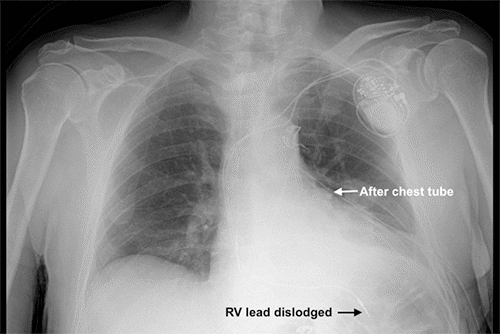

The patient was brought back to the operating room for placement of a dual chamber pacemaker via his left subclavian vein under monitored anesthesia care. The vein was accessed on the first attempt using anatomic landmarks. But, with the patient under monitored anesthesia care, it was not possible to have him hold his breath as the needle was inserted. There were no issues when we were threading the guidewires. We made a few adjustments with the right ventricle (RV) lead to find a suitable location for lead placement, but overall it was a routine pacemaker procedure. A portable chest X ray (CXR) was obtained about 15 minutes later in the recovery room and was negative for pneumothorax (PTX) (Figure 1). About three or four hours later, the pacemaker technologist interrogated the device, and all parameters were appropriate, so the patient was discharged home. Our institution had been moving toward same-day discharges unless there were other reasons to keep the patient overnight, but this patient lived nearby and was comfortable with discharge.

Figure 1. Immediate Postoperative Chest X Ray (CXR). Published with Permission

Image depicting placement of dual-chamber permanent pacemaker via left subclavian vein.